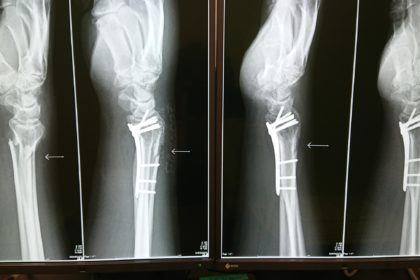

さて、昨日のブログで治り具合を報告しましたが、再手術の日程が決まりました!

9月25日に、レントゲンに写ってるプレートを取ります!

本日整形外科を受診したので、並べてみました。

回復の仕方、解りますかね?